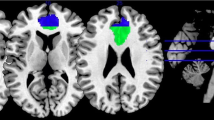

ROI construction

We defined the PCC ROI using the Harvard–Oxford Structural Probability Atlas (thresholded at 50% probability, Fig. 1) distributed with FSL neuroimaging analysis software (http://fsl.fmrib.ox.ac.uk/fsl/fslwiki/Atlases). The mean probability for the PCC was over 70% (M ± SD: 70.53 ± 15.01) and the centroid (located at MNI coordinate 0, – 35, 33) was 96%. The total volume for the PCC was 10,816 voxels. Centroid, average threshold, and volume statistics were gathered using Mango’s ROI analysis and histogram capabilities as well as FSL’s ‘fslstats’ utility (http://ric.uthscsa.edu/mango, http://fsl.fmrib.ox.ac.uk/fsl/fslwiki/Fslutils?highlight=%28fslstats%29). Prior to use in the following meta-analyses, the PCC ROI was binarized using FSL’s ‘fslstats’.

Dorsal–ventral PCC

Because previous studies have reported neurofunctional differences between the dorsal and ventral portions of the PCC (Bzdok et al. 2015; Leech et al. 2011), we created dorsal/ventral PCC ROIs for use in exploratory meta-analyses. Here we defined the dPCC ROI as the region of the posterior cingulate associated with areas 23c, 23d, d23, and adjacent area 31 and the vPCC ROI as the portion of the PCC associated with v23 and caudal area 31, in line with previous research (Vogt et al. 2006; Yu et al. 2011). We used FSLeyes (https://fsl.fmrib.ox.ac.uk/fsl/fslwiki/FSLeyes) to construct the dPCC and vPCC ROIs. Within FSLeyes, we used the atlas panel to search for “posterior cingulate”. From the search results we selected bilateral regions of the posterior cingulate specific to Brodmann Areas (BAs) 23 and 31 and exported the overlays. These overlays were then opened in Mango and assembled into a single ROI. To differentiate the dPCC and vPCC subregions, we divided the PCC ROI, inclusive of BAs 23 and 31, along the ventral branch of the splenial sulcus, which has been previously established as the cytological and functional border of the dPCC and vPCC regions (Yu et al. 2011; Fig. 1).

The PCC, dPCC, and vPCC ROIs were exported for use in the following meta-analytic procedures.